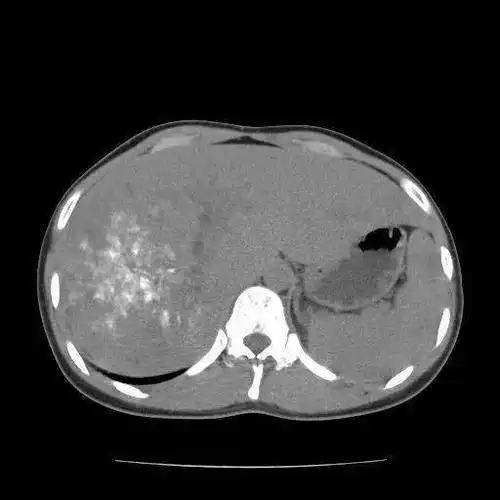

肝包虫(泡状棘球蚴)